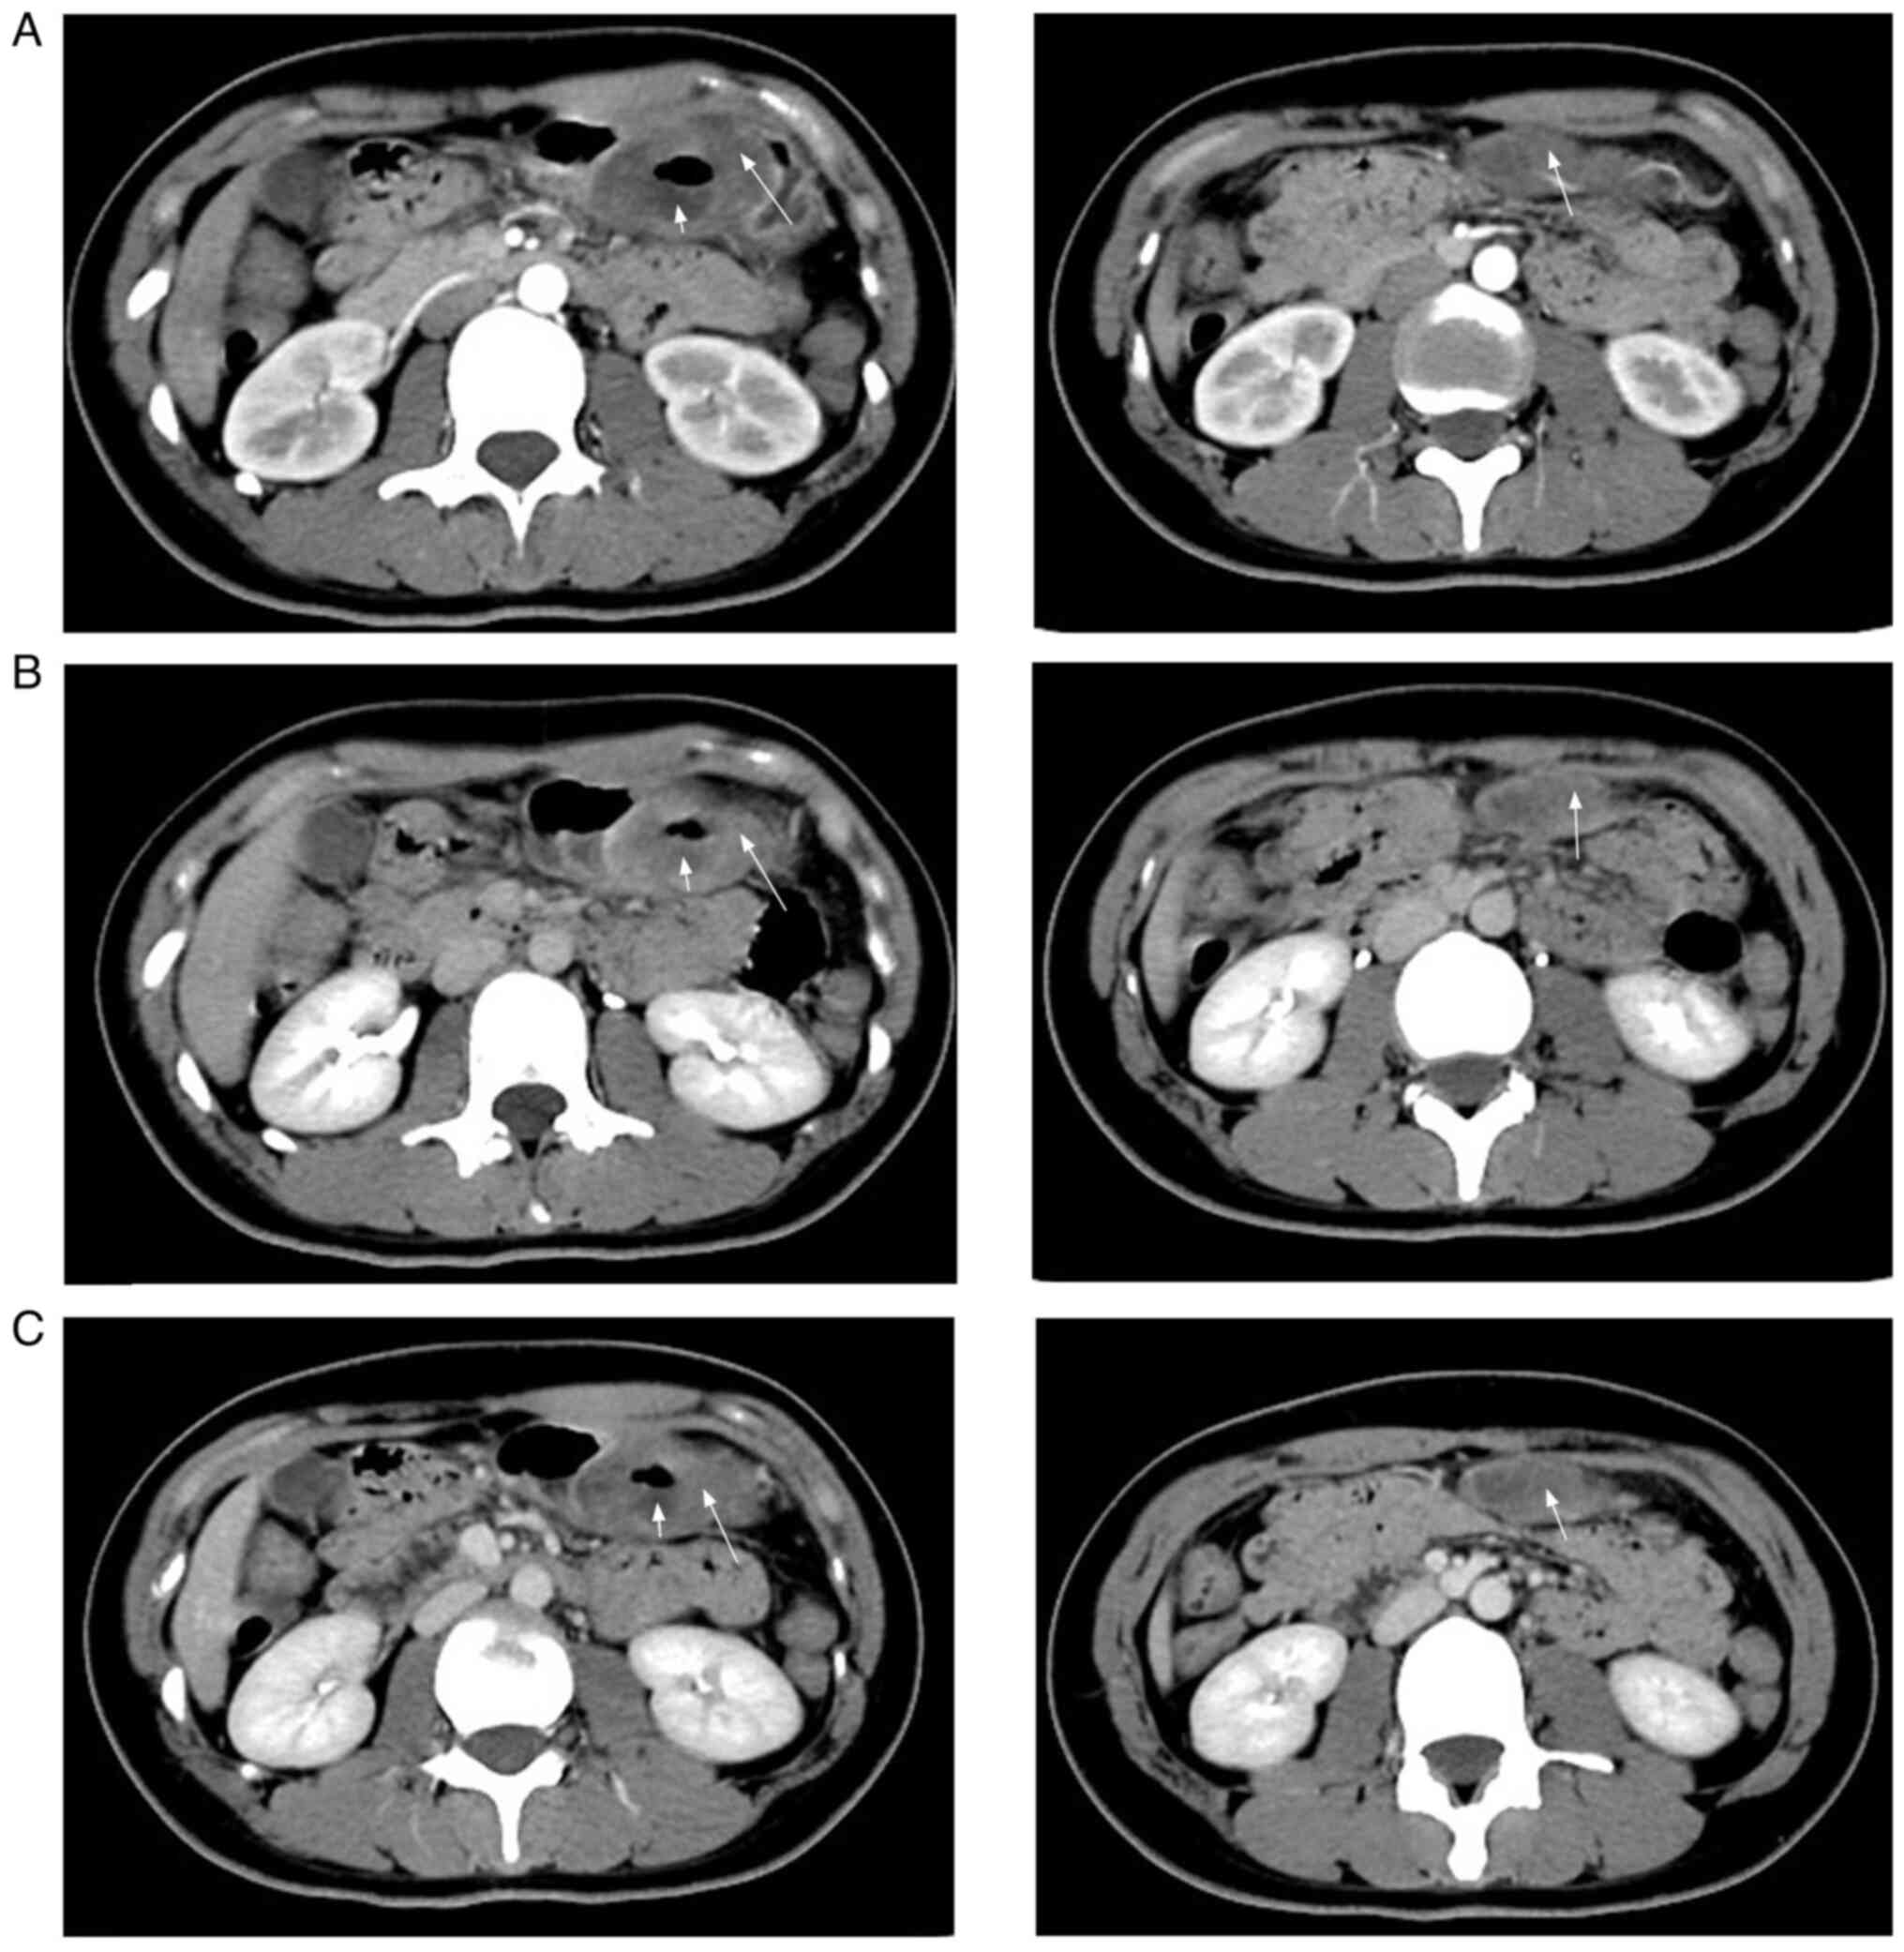

A healthy 20-year-old female patient visited Handan Central Hospital in March 2021 with intermittent abdominal pain for >1 month, which was noticeable after meals and gradually worsened, accompanied by melena. The physical examination revealed no specific findings. The iron level was 2.5 µmol/l (reference range, 7.8-32.2 µmol/l). Gastroscopy revealed a 2.5-cm deep ulcer on the side of the lower greater curvature of the gastric body. The ulcer was covered with white moss and the surrounding mucosa was edematous. The biopsy tissue pathology revealed a neuroendocrine tumor. An abdominal enhancement computed tomography (CT) scan showed a thick and ulcerated distal wall of the gastric body bulging into the gastric cavity (>4.5×2.0 cm). A deep depression with poorly defined borders was also evident (Fig. 1A). In the venous (Fig. 1B) and equilibrium (Fig. 1C) phases, the ulcer was not strengthened, whereas the peripheral parenchyma was slightly strengthened. A round nodule with uneven density, slight hypointensity in the middle and well-defined borders was detected beneath the lesion (Fig. 1A). Enhancement scans revealed curved enhancement at the nodal edges. In the coronal scans, the second lesion was poorly demarcated from the gastric mucosa, and the two lesions were connected in the coronal position in the venous phase (Fig. 2). It was difficult to establish whether it was an enlarged lymph node or a tumor protruding from the gastric body. Considering the age of the patient and the present illness, the imaging diagnosis revealed lateral displacement of the greater curvature of the stomach with malignant difficulty.

Figure 1.

Abdominal enhancement computed tomography scans (axial sections). (A) Axial arterial phase image showing the thickened distal wall of the gastric body (left long arrow) and an ulcer (left short arrow), and a hypodense nodule (right arrow) below the stomach. (B) Axial delayed-phase image showing mild enhancement (long arrow) and no strengthening (left short arrow). (C) Axial venous phase image showing slight strengthening (long arrow).